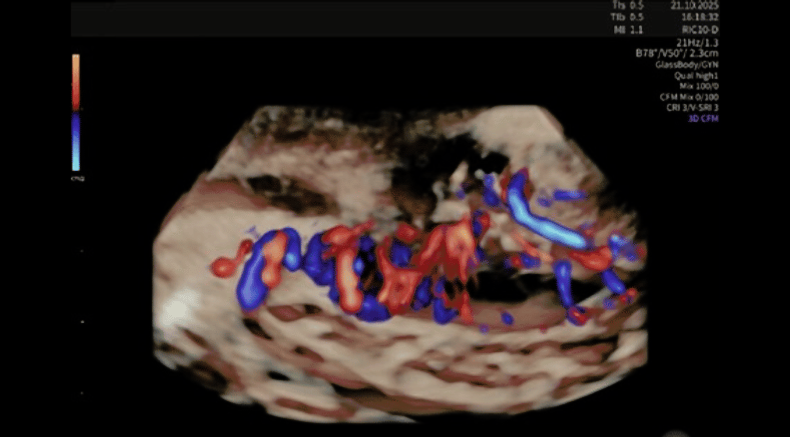

HDlive GlassBody 3D rendering with integrated color Doppler flow mapping, showing hypoechogenic nodule with marked intralesional vascularity

Barra, F., Maramai, M., Olcese, F., Beleva, D., Gustavino, C. and Ferrero, S. (2026), Decidualized posterior compartment deep endometriosis: three-dimensional rendering and Doppler-based vascular assessment. Ultrasound Obstet Gynecol. https://doi.org/10.1002/uog.70225